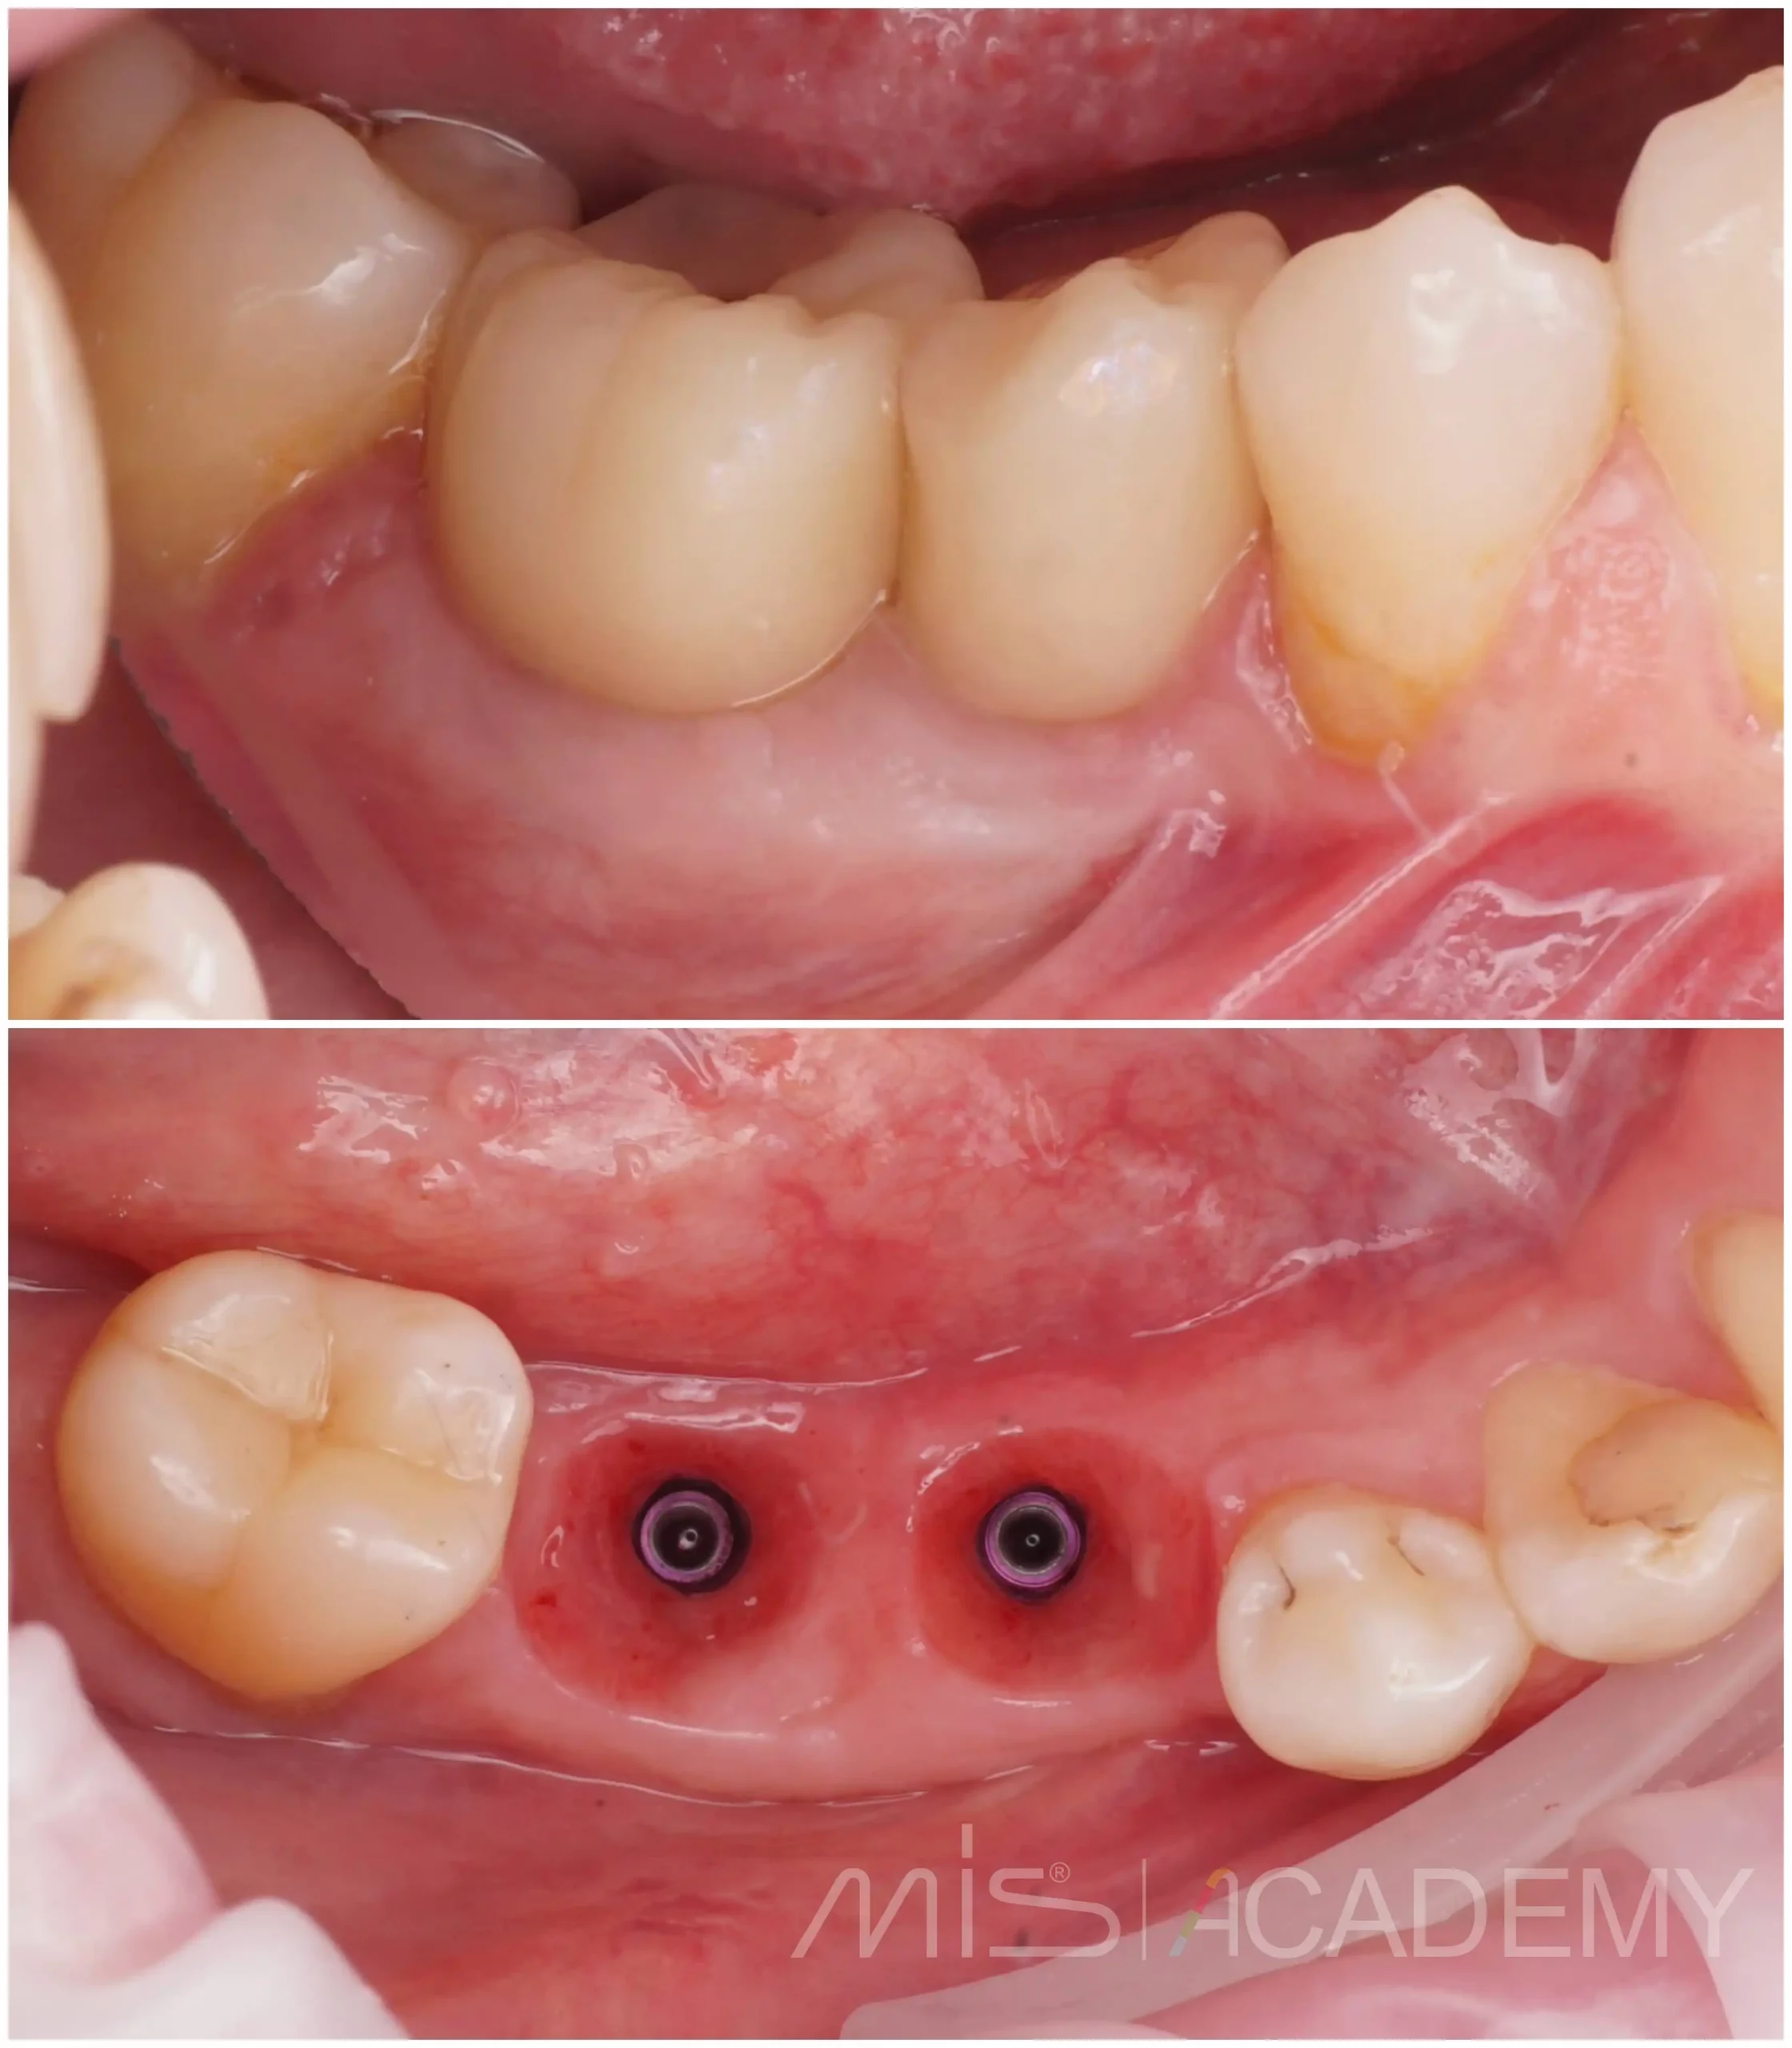

Через 2 месяца повторный этап:

— Открытие имплантатов.

— Замена формирователей на concave фдм.

— Повторная работа с мягкими тканями для формирования стабильного и прогнозируемого контура.